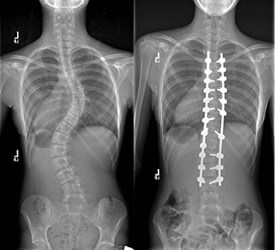

Skolyozun cerrahi tedavisinde amaç; omurgadaki eğriliğin daha da fazla ilerlemesini engellemek ve omurgayı en güvenli şekilde düzeltmektir. İlerlemenin durdurulması, yaşamın ilerleyen yıllarında ağır skolyozla birlikte olan ciddi sağlık sorunlarını engelleyecektir. Ameliyat sırasında eğrilik, güvenli bir düzeltmenin mümkün olabileceği en yüksek oranda düzeltilir. Bunu yapmak için implantlar, eğriliğin olduğu omurga kısmındaki omurlara tutturulur. Daha sonra çeşitli maniplasyonlarla omurga eğriliği düzeltilir. Ameliyat sonrasında ertesi gün ayağa kaldırılan hastaya günlük yürüme egzersizleri verilir. Hastalarımız 3-7 gün arasında hastanede kalmaktadır.

Bu ameliyatlarda Spinal Navigasyon ve Nöromoniterizasyon cihazları kullanılarak sinirlerde herhangi bir zarar oluşması engellenmektedir.